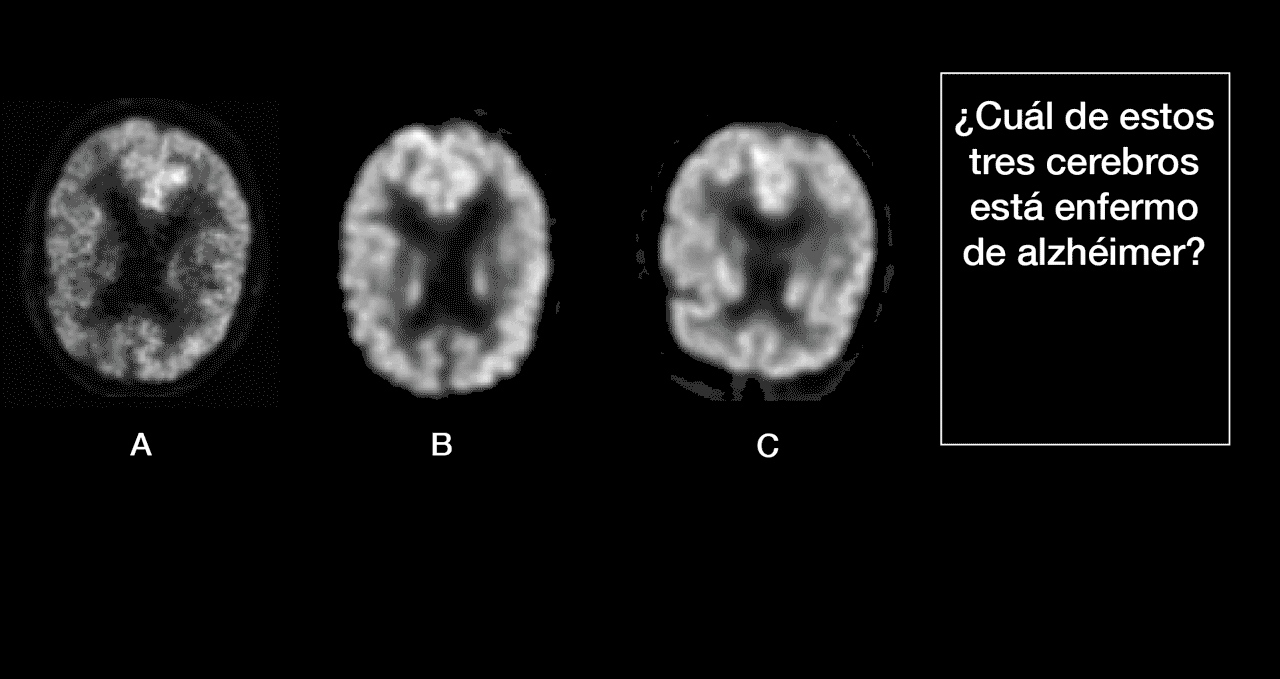

Alzheimer,

Alzheimer #12

Tags: Alzheimer #12, #886